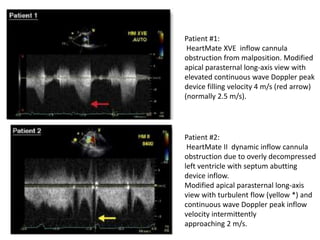

• Abnormal LVAD cannula Doppler findings:

• LVAD dysfunction may be indicated by built-in

alarm systems that sense low pump rates caused

by various mechanisms of cannula obstruction.

• These include cannula thrombus, partial inlet

occlusion by adjacent myocardial trabeculations,

cannula angulation into the myocardium or other

cannula malposition caused by LV underfilling,

and inlet or outlet kinking.

• For pulsatile pumps, a peak inflow velocity 2.5

m/s or intermittent interruptions of the usual

laminar cannula inflow is indicative of inflow

cannula obstruction.

• In contrast, for continuous-flow pumps, a peak

inflow velocity 2 m/s with associated

turbulent flow may represent either inflow

cannula obstruction, malposition, or improved

LV systolic function.

Patient #1:

HeartMate XVE inflow cannula

obstruction from malposition. Modified

apical parasternal long-axis view with

elevated continuous wave Doppler peak

device filling velocity 4 m/s (red arrow)

(normally 2.5 m/s).

Patient #2:

HeartMate II dynamic inflow cannula

obstruction due to overly decompressed

left ventricle with septum abutting

device inflow.

Modified apical parasternal long-axis

view with turbulent flow (yellow *) and

continuous wave Doppler peak inflow

velocity intermittently

approaching 2 m/s.